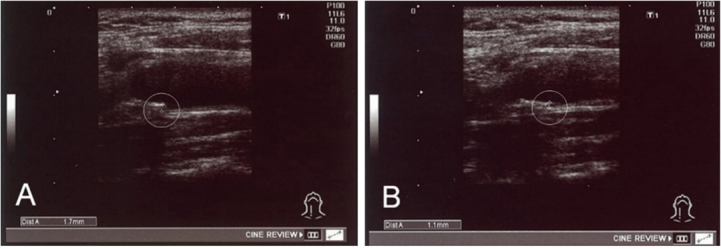

18 例臨床研究前 IMT 值異常的患者,接受此次臨床研究后 IMT 值顯著下降(p < 0.01)。其中,一名 56 歲男性患者在 Ad-MSC 治療前 ( a ) 和治療后 ( b ) 的頸總動(dòng)脈 IMT 示例顯示,治療后近 4 個(gè)月,IMT 從 1.7 毫米下降至 1.1 毫米。